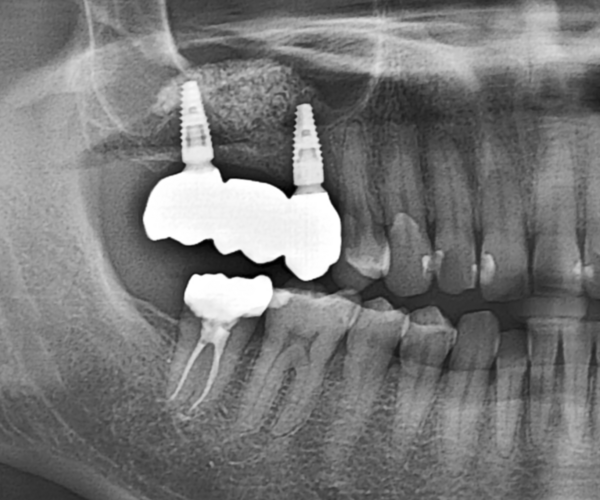

治療の経緯

右上の歯が取れたので、噛めるようにしたい

治療方法

奥歯は歯根破折していたため、抜歯をし、骨が少なかったため上顎洞にサイナスリフトを行い、骨を補填してインプラントを埋入しました。インプラントブリッジにて被せ物を作りました。

治療期間 動的期間6ヶ月

費用 インプラント埋入2本 600,000円

サイナスリフト  330,000円

セラミックのブリッジ(クラウン3本分)  450,000円

合計   1,380,000円

治療によるリスク インプラントは歯周病に弱いため、歯周病にかかると悪化する可能性があります